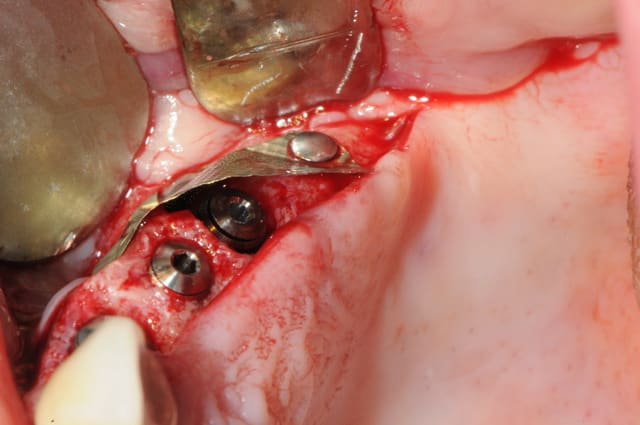

la tête est entièrement recouverte et sous la membrane je mets de l'os parcellaire ou du bio mat

je puis t'assurer que c'est de l'os sous la membrane quand on la retire. sinon, ça fait très longtemps que je ne l'utiliserai plus.

en ce qui concerne le nombre de clous; il semble qu'il y en ait beaucoup, mais la morphologie réelle de l'os et la difficulté à reconstruire un tel volume est difficilement visible avec des photos.